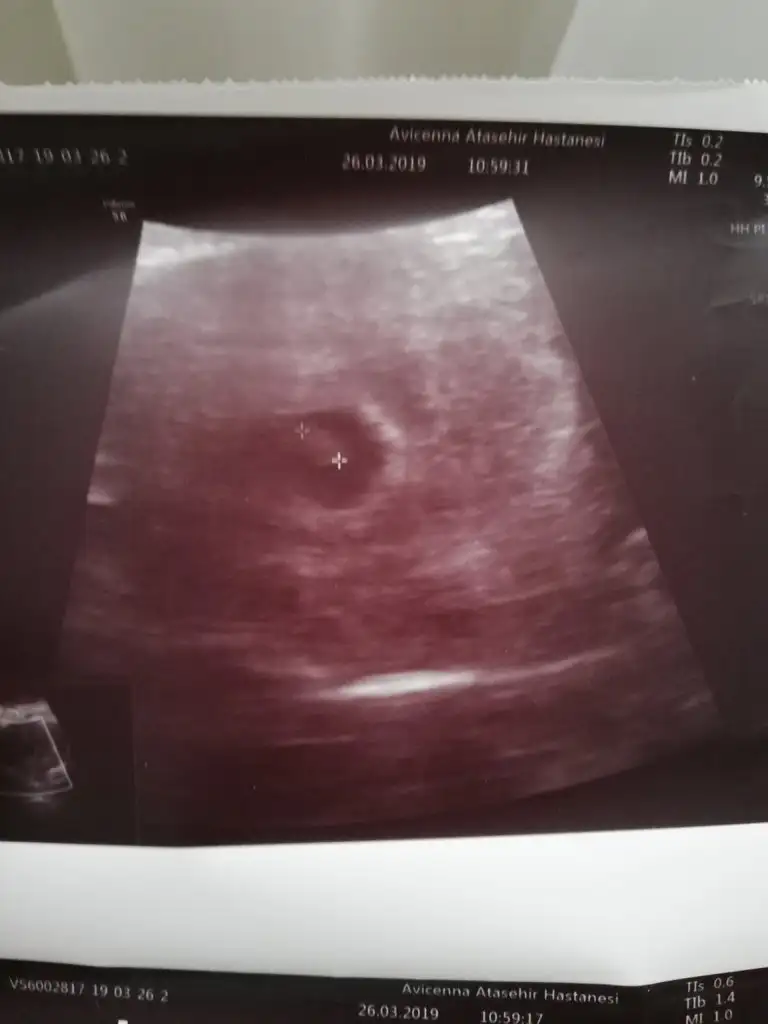

6+1 haftalık bende yorum alabilirmiyim :)